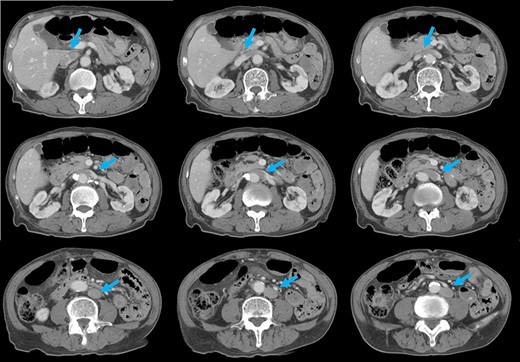

Preoperative computed tomography (CT) revealed a tumor in the sigmoid colon accompanied by some regional lymph node swelling (Fig. 1). It also showed that the IVC ascended vertically along the left side of the abdominal aorta. After connecting with the left renal veins, the left-sided IVC crossed the abdominal aorta anteriorly to join the normal prehepatic segment of the IVC (Figs 2 and 3). Coronal CT showed that the descending colon misplaced at the abdominal midline and the sigmoid colon in the right upper abdomen (Fig. 4). The preoperative diagnosis was thus sigmoid colon cancer with left-sided IVC and PDM.

Coronal reformation of the CT image shows precisely how the left-sided IVC (arrows) ascended vertically along the left side of the abdominal aorta and crossed anterior to the aorta.